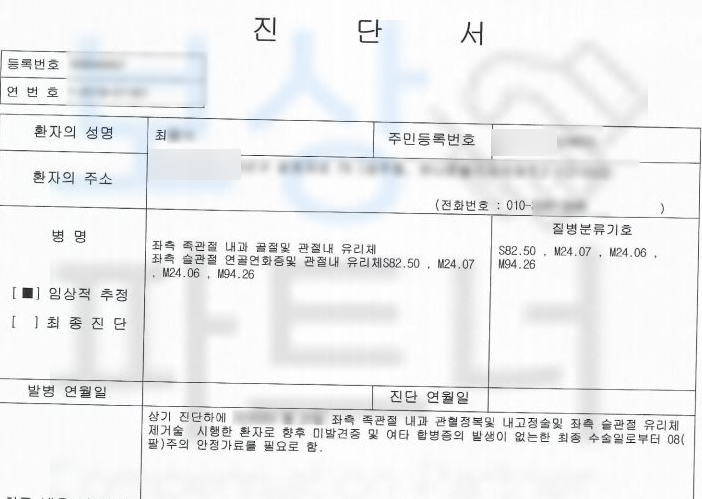

족관절 내과 골절 및 관절 내 유리체에 손상을 입었고 s8250 핀 고정술을 받아야 했습니다.

족관절의 약간의 장해 5% 해당하였죠.

의뢰인의 복사뼈 골절이 관절면까지 손상되어